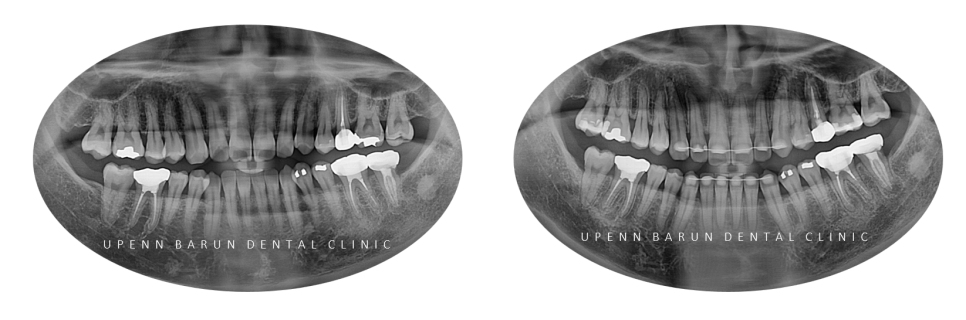

교정기간 21/4~24/3

반대교합이 개선되며 치열이 가지런해졌습니다.

교정을 시작하기 앞서

같은 원장님께 교정, 충치치료까지 가능한

유펜바른치과에서

충치치료를 마무리 해드리고 교정을 진행해드렸습니다 :)